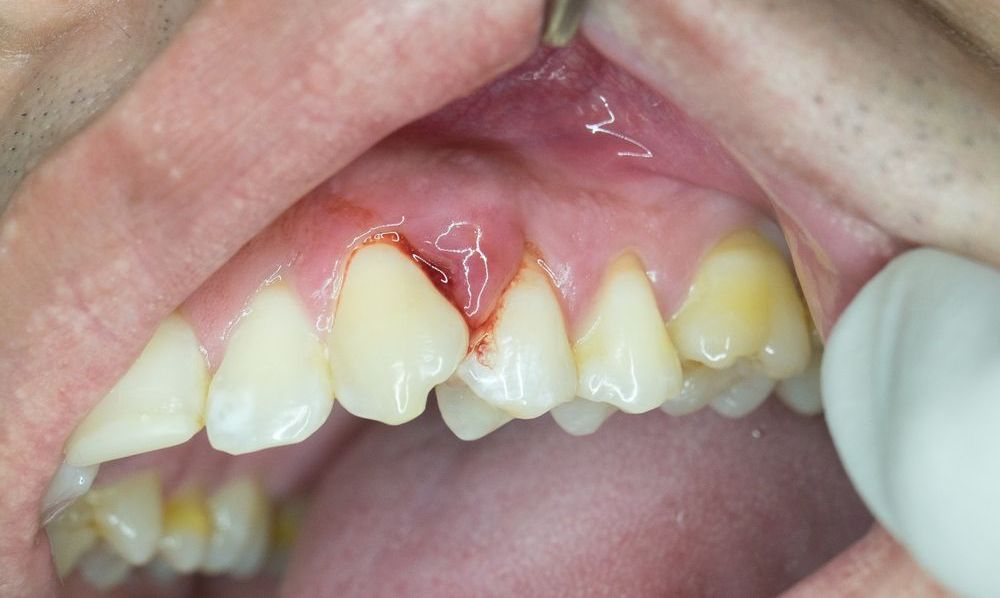

La enfermedad periodontal es una afección en las encías, que en su última etapa, puede disolver el hueso que mantiene a los dientes en su lugar.

No suele presentar síntomas, por lo que es una enfermedad silenciosa que en muchas ocasiones se detecta muy avanzada. Sin embargo, existen algunos indicios que pueden indicarte si tienes esta enfermedad:

• Encías rojas, inflamadas y suaves.

• Sangrado al cepillarte.

• Encías alejadas de los dientes.

El sarro, placa bacteriana entre los dientes, si se acumula demasiado se convierte en arenilla dura, llena de bacterias, que se esparce a la encía y la infecta. Esto se conoce como gingivitis, la forma más leve de la enfermedad periodontal.

Cuando este proceso avanza, se forman bolsas periodontales entre la encía y los dientes, que afectan al hueso maxilar, encargado de sujetar los dientes. Aquí ya se convierte en periodontitis leve, segunda etapa de la enfermedad.